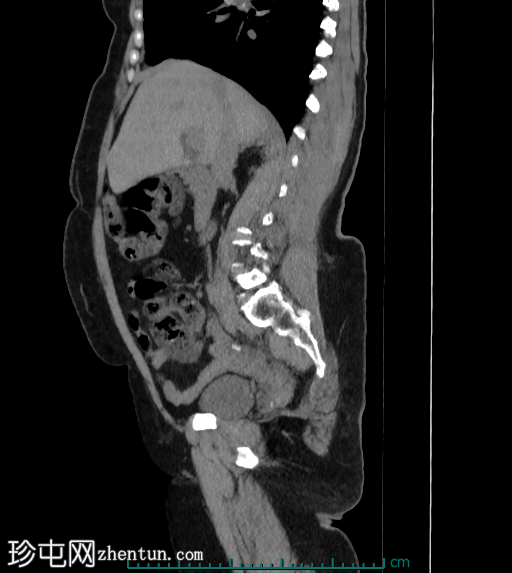

矢状位最大强度投影(MIP)

平扫

阑尾中段可见一放射性不透光阑尾粪石(冠状位和矢状位图像均可见),导致远端扩张。阑尾尖端直径达10 mm,呈充满液体的形态,周围可见脂肪条索,提示阑尾尖端炎。阑尾近端外观正常。

CT 扫描显示近端阑尾正常,而远端扩张,并伴有阑尾周围脂肪条索影。阑尾尖端可能出现局灶性壁增厚、阑尾粪石阻塞、阑尾周围积液以及区域淋巴结肿大。或者,阑尾移行点可能出现管腔狭窄、管壁增厚。盲肠通常正常,近端阑尾也正常。